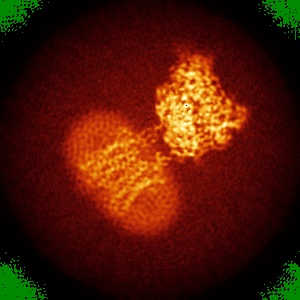

Cryo-EM structure of human GABA(B) receptor bound to the positive allosteric modulator rac-BHFF

Sample: Gamma-aminobutyric acid type B receptor

Fitted models: 7ca3